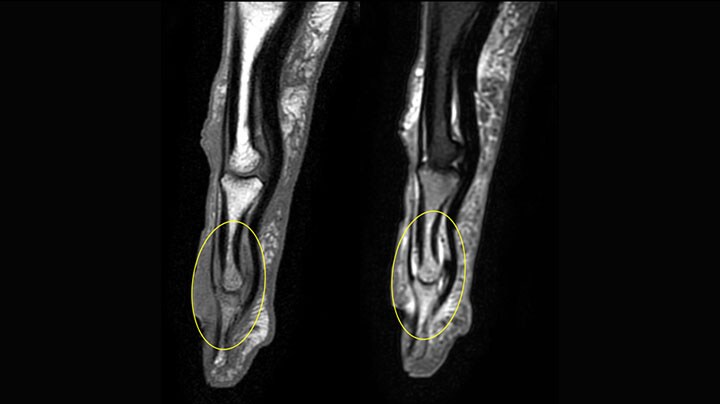

MRI examination on Prodiva 1.5T of a 72-year-old female with a malignant melanoma in the ankle. mDIXON TSE provides excellent fat suppression, without the distortion that is often seen at such extremities.